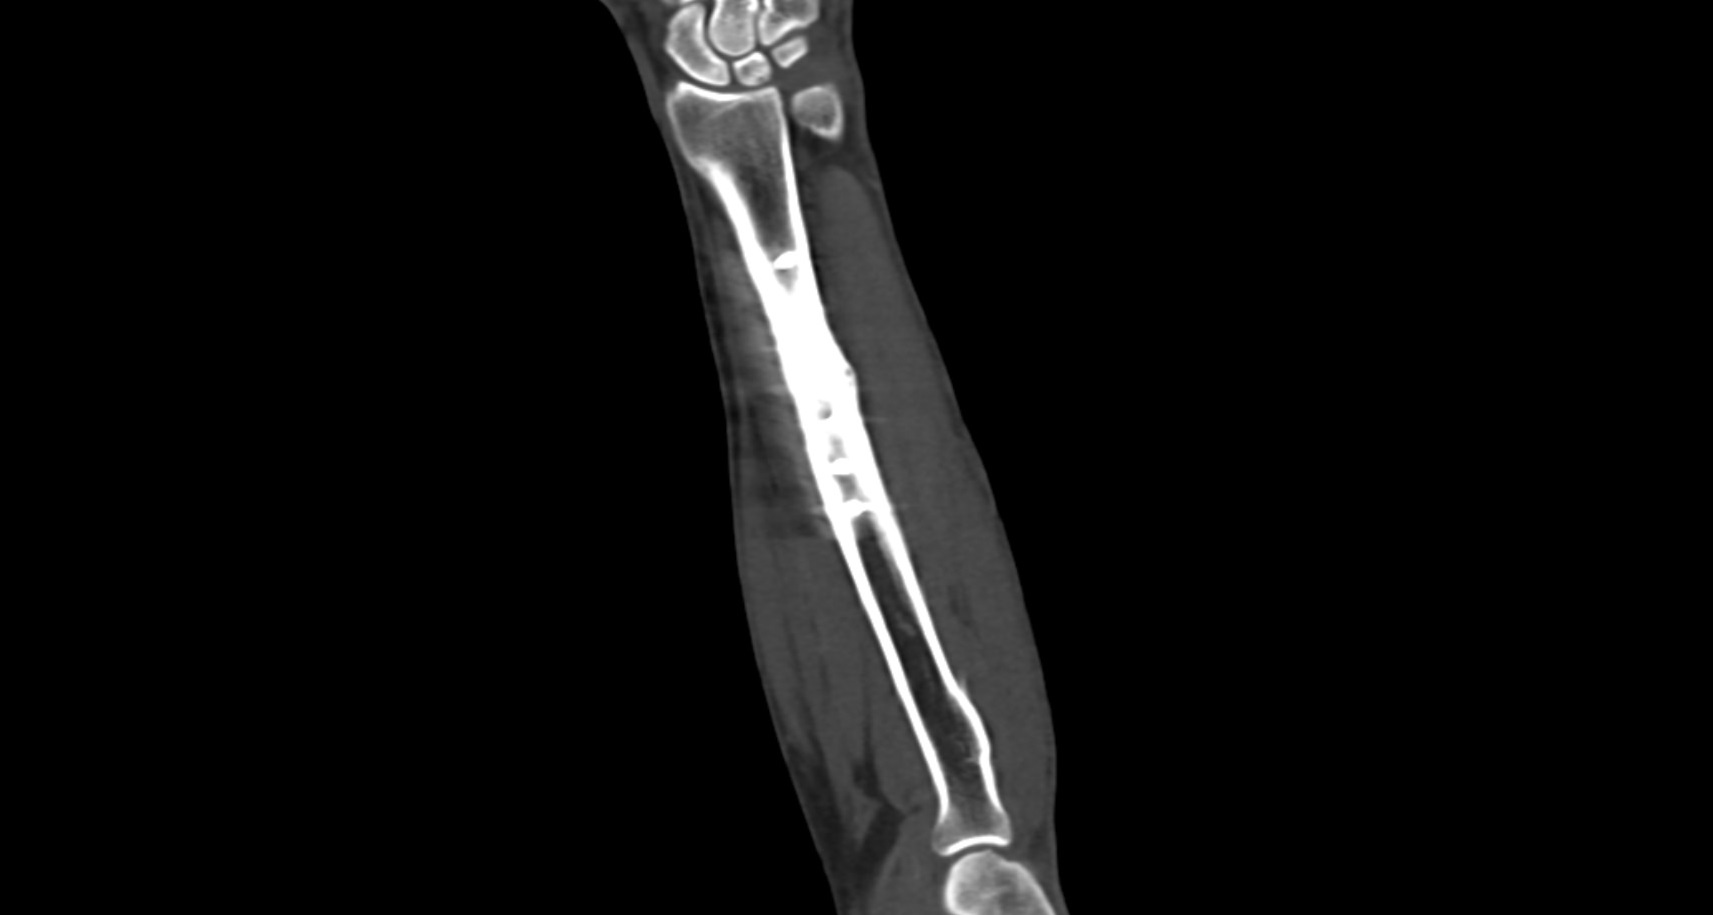

В диагностических центрах «Доступная медицина» сканирование области предплечья проводится на современных мультиспиральных компьютерных томографах экспертного класса TOSHIBA AQUILION. Аппараты при помощи рентгеновских лучей послойно сканируют исследуемую область, делая одномоментно множество тончайших срезов толщиной от 0,5 мм. В результате получаются детализированные изображения высокого уровня четкости и контрастности, при этом томографы обеспечивают минимум лучевой нагрузки на организм пациента.

Полученные при сканировании данные в дальнейшем проходят цифровую обработку, и на их основе создаются трехмерные изображения области предплечья.

Мультиспиральная КТ позволяет диагностировать деформации костей на фоне аномалий развития, различные вывихи, переломы костей предплечья, ушибы мягких тканей и надкостницы. КТ помогает обнаружить участки деструкции костной ткани, воспалительные изменения, опухолевые процессы. Результаты КТ дают информацию для хирурга и травматолога перед операцией о расположении осколков кости, а после операции позволяют оценить правильность репозиции костных отломков, проследить процессы регенерации кости, вовремя выявить различные осложнения (воспаление, смещение отломков, очаги деструкции костной ткани).